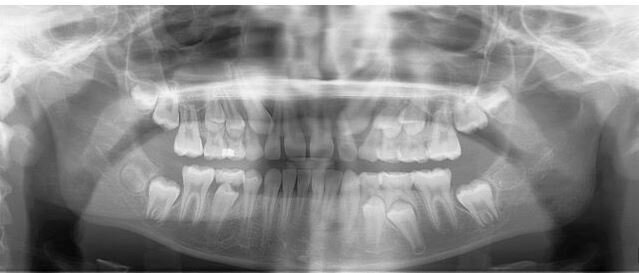

• Radiografía panorámica:  como lo indica su nombre permite obtener una vista completa de la boca incluyendo dientes, huesos y encías.